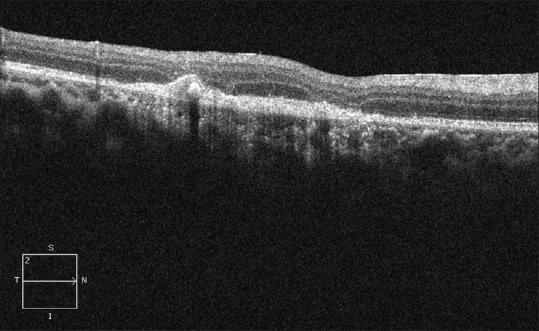

Diffuse unilateral subacute neuroretinitis (DUSN) is a subacute outer retinal inflammation due to the presence of a subretinal worm. The worm is identifiable in only 30% of the cases. The identification of the worm and laser photocoagulation of the worm remains the mainstay of treatment. Here, we describe a case of DUSN with a subretinal worm in the macula which was captured on Optical coherence tomography (OCT) scans and treated with laser photoooagulation.

弥漫性单侧亚急性神经视网膜炎(DUSN)是一种由于视网膜下存在蠕虫而导致的亚急性外层视网膜炎症。仅30%的病例中可识别出蠕虫。识别蠕虫并对其进行激光光凝仍是主要的治疗方法。在此,我们描述一例黄斑区视网膜下有蠕虫的DUSN病例,该蠕虫在光学相干断层扫描(OCT)中被捕获,并接受了激光光凝治疗。